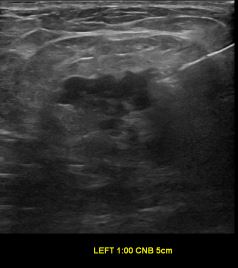

상기환자는 좌측 유방 만져지는 멍우리있어  내원하신 50대초반 여성분으로 의심스러운 좌측혹 조직검사 시행해 유방암으로 진단되었습니다